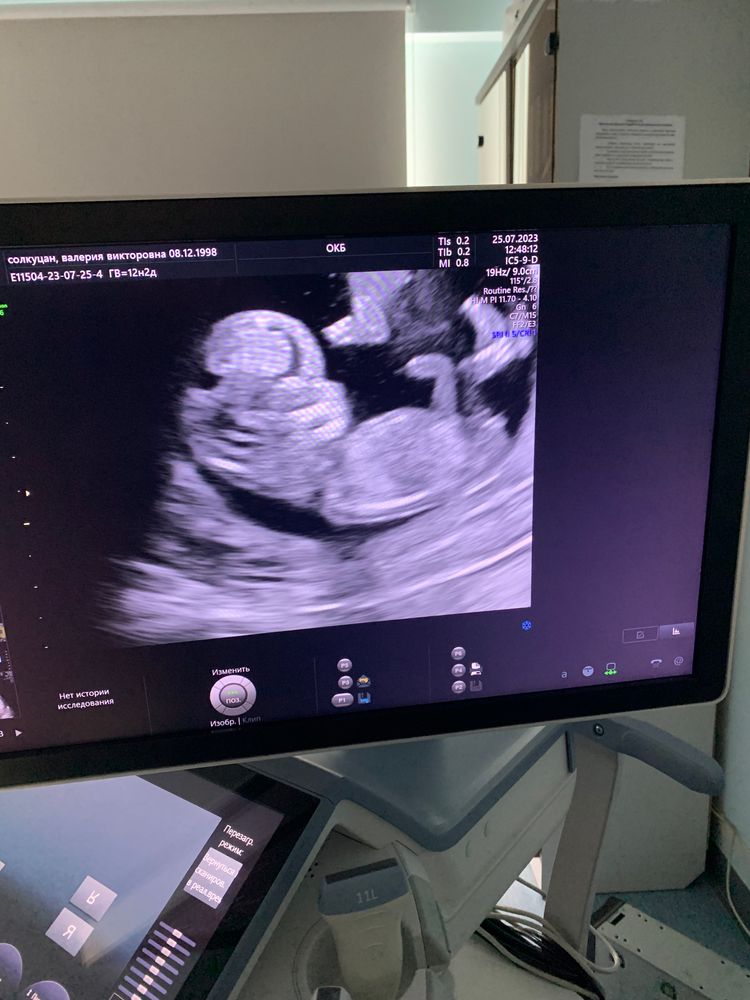

Мальчик или девочка?

Малыш похож на девочку )

Странный пост. 😁 узисту не доверяете , а нам доверяете ? Девочка )

Девочка

Мальчик.

У меня с таким половым бугорком был мальчик.

Девочка мне кажется ) Половой бугорок вдоль позвоночника.

Маришка, а здесь? Изображение

Валерия , и здесь )))

Маришка, узистка уверена что мальчик… а тут? Изображение

Валерия , у малышей на таком срок длина полового бугорка одинаковая, но разный наклон, вот по нему и смотрят) торчит - мальчик, вдоль позвоночника - девочка)

Валерия , ну раз специалист уверена, то лучше довериться её мнению. Она всё-таки столько лет этой работе посвятила, глаз уже должен быть намётан )

Валерия , 12 недель, как я поняла, у Вас срок? Не знаю, как везде, но, по крайней мере моя узист, на первом скрининге даже предположений не выдвигает,хотя она ооочень опытная☝️Только в этот раз мы с ней, уже зная, что по крови, сданной в Инвитро ,у меня сыночек, посмотрели половой бугорок и ее вердикт был: больше похоже на мальчика, вот на втором скрининге она уже уверенно сказала:мальчик💙Ну, а к вопросу в заголовке поста:мое мнение у Вас барышня🎀

Девочка🎀